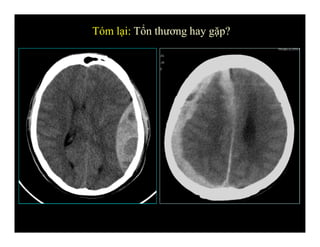

Tóm lại: Tổn thương hay gặp?